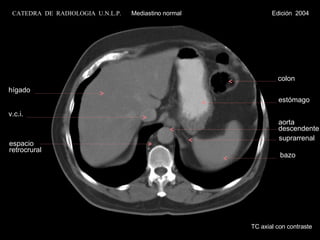

suprarrenal TC axial con contraste hígado v.c.i. espacio retrocrural colon estómago bazo aorta descendente CATEDRA  DE  RADIOLOGIA  U.N.L.P.   Mediastino normal  Edición  2004

suprarrenal TC axialcon contraste hígado v.c.i. espacio retrocrural colon estómago bazo aorta descendente CATEDRA DE RADIOLOGIA U.N.L.P. Mediastino normal Edición 2004